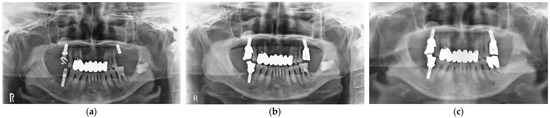

3.3. Clinical Outcomes

- Ogino, Y.; Matsushita, Y.; Sasaki, M.; Ayukawa, Y.; Koyano, K. A 3-Year Prospective Study on Radiographic Marginal Bone Evaluation Around Platform-Shifting Implants with Internal Conical Connections. Int. J. Oral Maxillofac. Implant. 2021, 36, 574–580. [Google Scholar] [CrossRef] [PubMed]